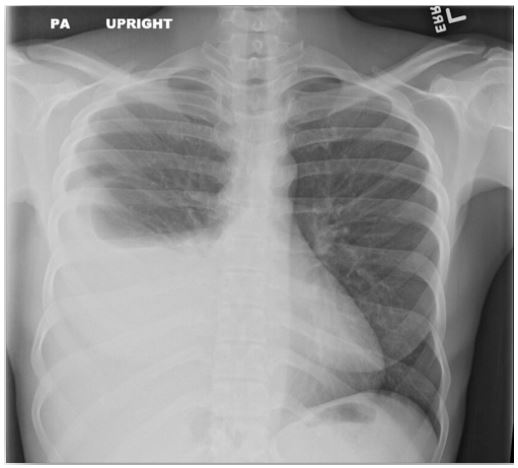

Figure 2: Chest X-ray revealed large right-sided pleural effusion.

On admission, her vitals were within normal limits. Physical exam revealed an ill-appearing female who appeared in mild discomfort with significantly diminished lung sounds over the right lower chest and dullness to percussion. Her abdomen was non-tender but was moderately distended with a positive fluid wave and shifting dullness. Other systems were unremarkable. Initial lab values showed microcytic anemia with Hgb of 7.6, but normal renal and hepatic function testing. Chest, Abdomen and Pelvis CT without contrast showed a moderate right hydropneumothorax, moderate to large pleural effusion without lung mass, as well as large ascites and heterogeneous uterus with questionable prominent cervix, and normal ovaries.